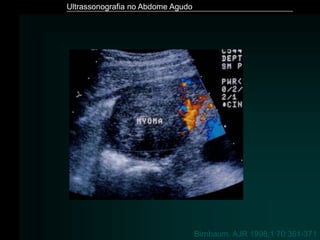

Birnbaum. AJR 1998;1 70:361-371

Ultrassonografia no AbdomeAgudo Birnbaum. AJR 1998;1 70:361-371

• #14 .

• #55 LEIOMIOMA SEM FLUXO AO DOPPLER – TORÇÃO OU DEGENERAÇÃO PACIENTE GESTANTE CONDUTA EXPECTANTE COM SINTOMÁTICOS PARA A DOR – EVOLUIU BEM.